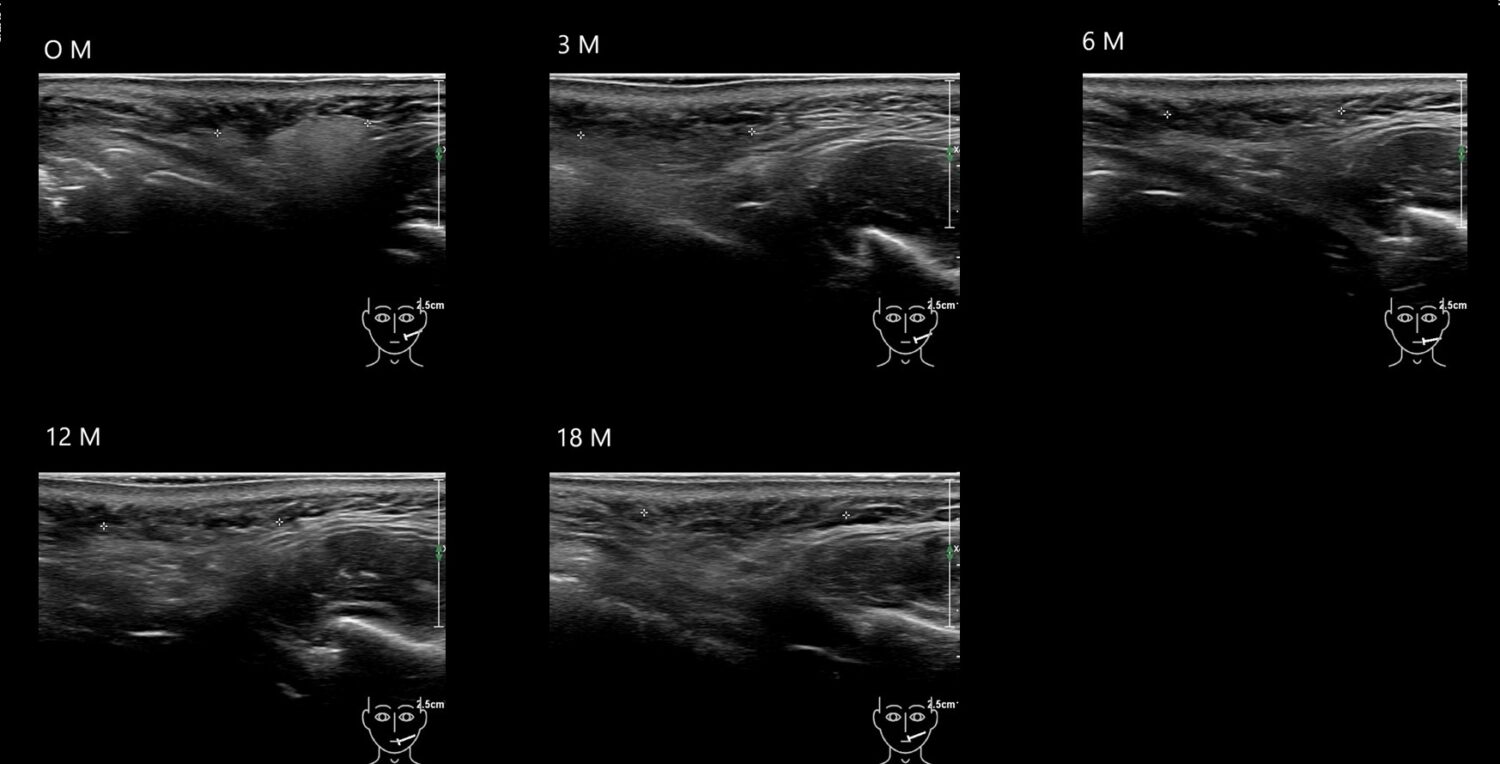

Filler library